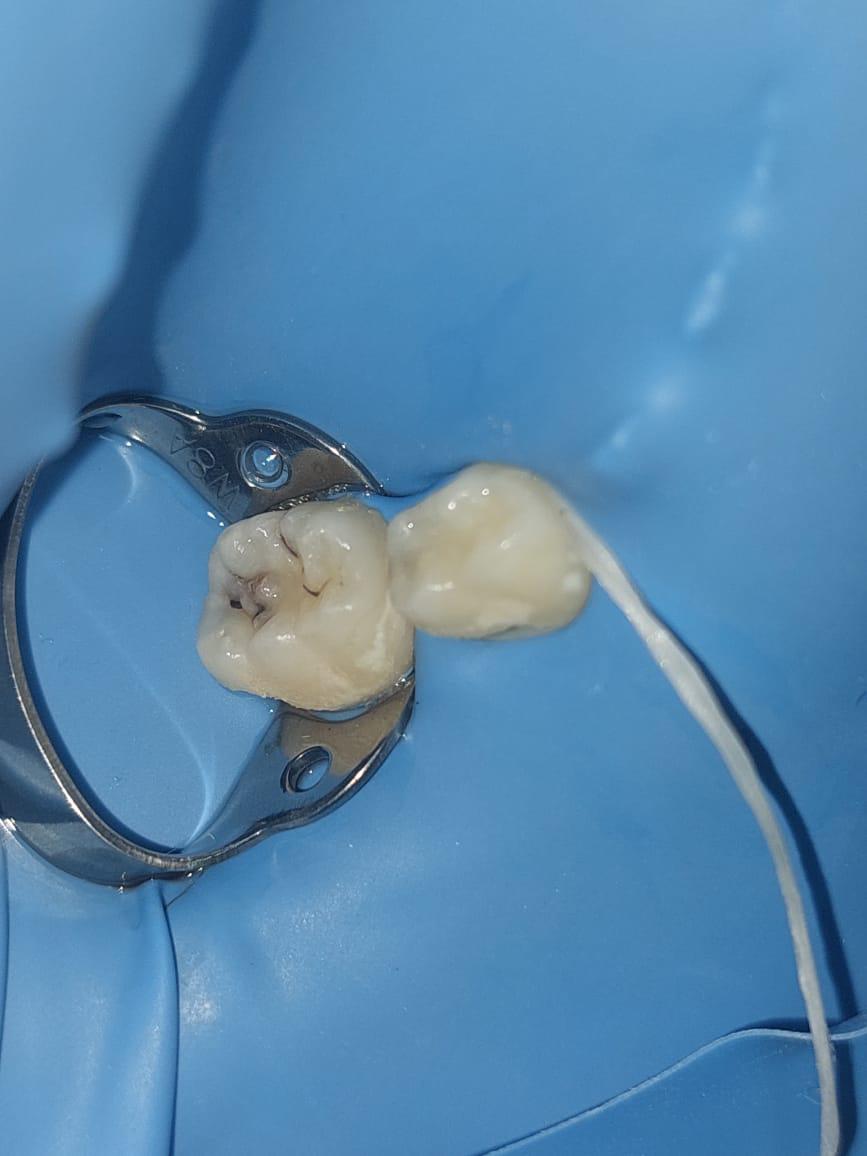

تجميل الضروس الخلفية و استعادة وظيفتها

استعادة وظيفة الضروس الخلفية و تجميلها